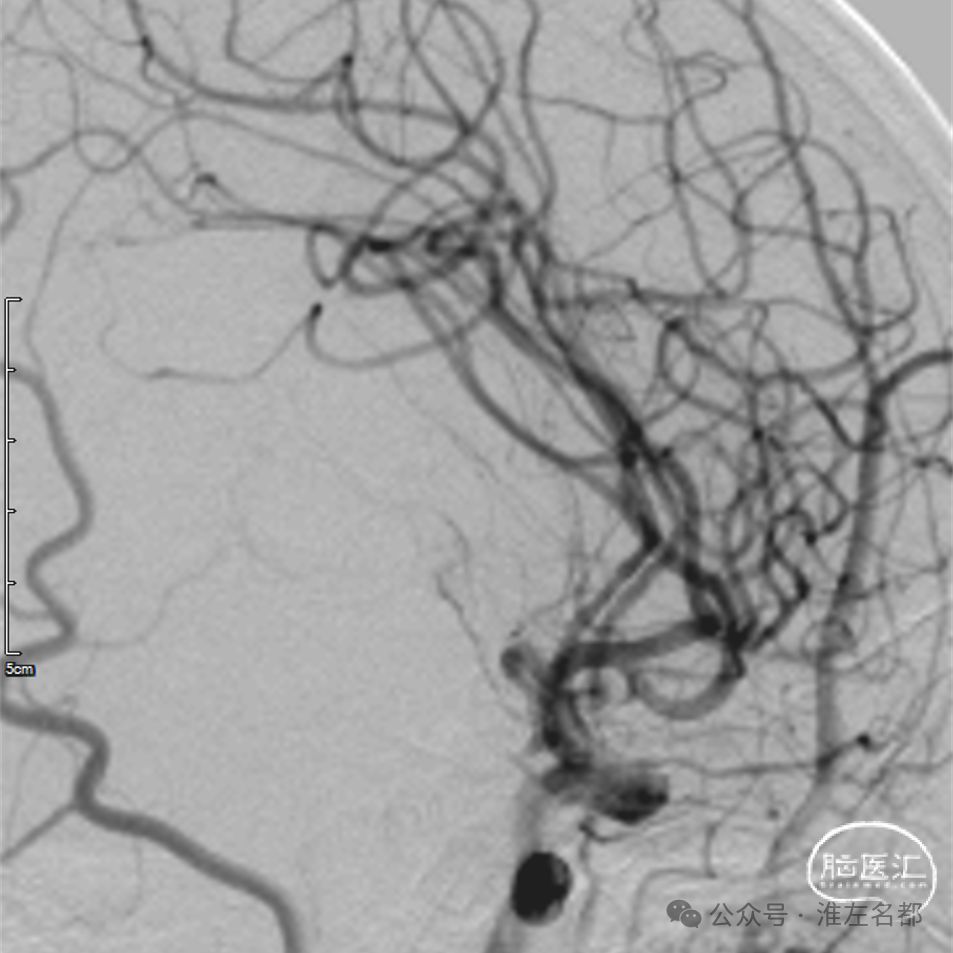

颅脑CTA:右侧大脑前动脉A2段局部管腔严重狭窄,右侧大脑前动脉A1段未发育,左侧大脑前动脉A1段粗大。

CTA:右侧大脑前动脉原A2段狭窄位置管腔闭塞。

脑CTP:右侧大脑前动脉供血区较大范围TTP显著延长。